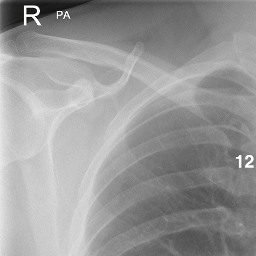

The posterior-anterior (PA) film.

(12) Right paratracheal line;